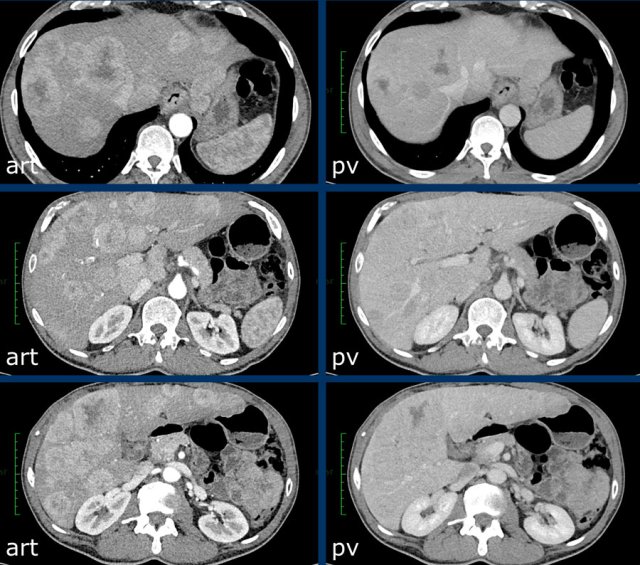

Here an image in the late arterial phase in a patient with cirrhosis.

There is an observation with non-rim hyperenhancement (yellow arrow).

In a late phase there is washout.

These are typical features of HCC.

The other lesion (green arrow) is a treated lesion, which we will discuss later.

Washout - Capsule

This is another patient with an enhancing lesion and washout.

Note also the enhancing capsule on the delayed phase.

A capsule is one of the major features of HCC and can be complete or partial.

A capsule should always be included within the measurement of the lesion.